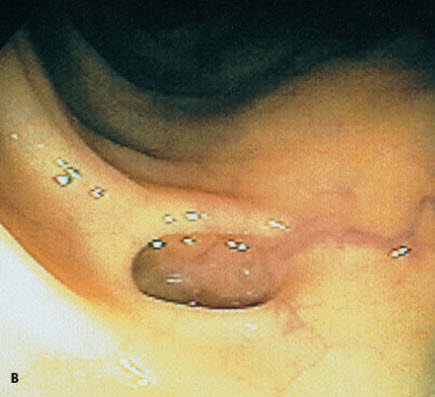

Extensive diverticulosis was found throughout the length of the colon of an 84-year-old woman, who depended on a weekly dose of magnesium citrate to have a bowel movement. Typical lesions are shown here (A and B). Diverticula may occur singly or clustered in small groups, with narrow or broad openings into the colonic lumen.

Diverticulosis rarely affects persons under age 40; however, its incidence increases dramatically with each succeeding decade. Although patients with this disorder are frequently asymptomatic, abdominal cramps, constipation, and flatulence may mark the presence of the disease.